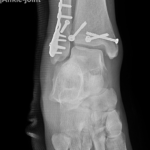

if the fracture is displaced, surgery may be needed to put the bone back into the correct position and fix the bone with Plates & screws or nails for adequate healing to occur.

- Ankle Fractures.